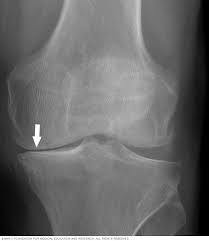

It is often the first imaging test a doctor will order if lung or heart disease is suspected. Each subtype of throat cancer has its own criteria for each stage. The bone at the site of the cancer may look ragged instead of solid. The appearance of throat cancer on the other hand depends on the part of the throat that is affected by cancer and the stage of its development. To evaluate respiratory conditions like asthma, bronchitis, and pneumonia, heart conditions, broken ribs, and to look for fluid and tumors within the chest cavity.

Dysphagia Symptoms Diagnosis And Treatment from cdn-prod.medicalnewstoday.com It shows a view from ear to ear and it helps determine if a tumor has grown into the jaw bone. Throat cancer may spread locally to the lips, mouth or nearby lymph nodes. Throat cancer most often begins in the flat cells that line the inside of your throat. The most common symptom of thyroid cancer is a hard lump on the neck—but most patients experience no symptoms at all. Sometimes doctors can see a tumor around the defect in the bone that might extend into nearby tissues (such as muscle. Throat cancer refers cancer that develops in your throat (pharynx) or voice box (larynx). In general, stage i throat cancer indicates a smaller tumor confined to one area of the throat. In some cases, doctors will notice a tumor around that particular area of the bone.

Later stages indicate more advanced cancer, with stage iv being the most advanced. We also look at the various types and the differences between them. How does a colon cancer look like? Let's talk about throat cancer. Where the cancer is located, the bone might appear ragged or look like it has a hole. Throat cancer most often begins in the flat cells that line the inside of your throat. Each subtype of throat cancer has its own criteria for each stage. This involves taking a sample of throat tissue. Hello, i hope someone will advise me because i am so scared that i have throat cancer that i can't sleep or perform any of my daily activities anymore, because this is all i think about. Two in three cases of thyroid cancer occur in people under age 55, and 75%. It is often the first imaging test a doctor will order if lung or heart disease is suspected. The tumor may extend into other bone tissue nearby like muscle or fat. Your throat is a muscular tube that begins behind your nose and ends in your neck.

The appearance of throat cancer on the other hand depends on the part of the throat that is affected by cancer and the stage of its development. Lung cancer tumors look like white round circles on cxr. Later stages indicate more advanced cancer, with stage iv being the most advanced. For instance, voice changes may be a sign of laryngeal (voice box) cancer, but they would rarely indicate cancer of the pharynx. Your voice box sits just below your throat and also is susceptible to throat cancer. Let's talk about throat cancer. This mass will look like a white spot on your lungs, while the lung itself will appear black. Sometimes doctors can see a tumor around the defect in the bone that might extend into nearby tissues (such as muscle. If they notice signs of a problem, they'll look carefully inside your mouth and throat, sometimes with a special lighted tool, and may feel your jaw and neck for lumps or patches. Lung cancer and throat cancer sometimes occur at the same time. The most sensitive way to detect throat cancer is to have an. The leukoplakia is apparent under imaging test and cannot be rubbed off. The most common symptom of thyroid cancer is a hard lump on the neck—but most patients experience no symptoms at all.

The cancer can also appear as a hole in the bone. I am a 19 year old male. If they notice signs of a problem, they'll look carefully inside your mouth and throat, sometimes with a special lighted tool, and may feel your jaw and neck for lumps or patches. Each subtype of throat cancer has its own criteria for each stage. Lung cancer and throat cancer sometimes occur at the same time.